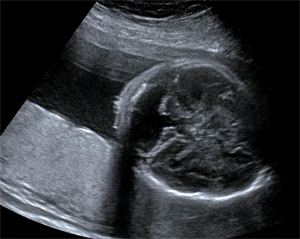

UCSF doctors in ultrasound are also expert in fetal thoracic and abdominal pathologies, including gastroschisis, omphalocele, lung sequestration, and cystic adenomatoid malformation (congenital pulmonary airway malformation) and congenital high airway obstruction (CHAOS). We assist in fetal operations for these anomalies by providing guidance for radiofrequency ablation, laser ablation for Twin-Twin Transfusion Syndrome, fetal blood transfusions, fetal lung mass resections, tracheal balloon placement and fetal surgery for Spina Bifida. (Open myelomeningocele)